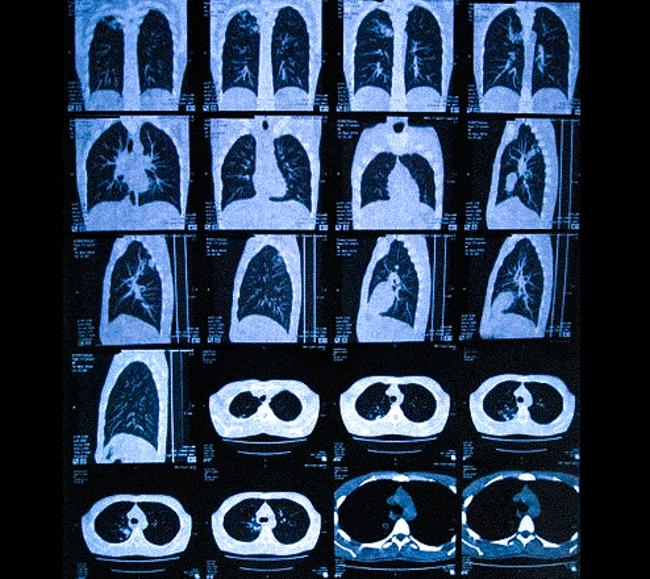

Признаки застойной пневмонии на КТ

Компьютерная томография — метод многослойной визуализации внутренних органов. В результате сканирования врач получает фотографии поперечных срезов грудной клетки. На снимках светлые участки соответствуют плотным структурам, мягкие ткани дают гиподенсный сигнал.

КТ-изображения легких в разных проекциях (фронтальная, сагиттальная, аксиальная)

С помощью специализированного программного обеспечения врач может восстановить как прямые, так и боковые проекции, а при необходимости – создать трехмерную модель органов грудной клетки.